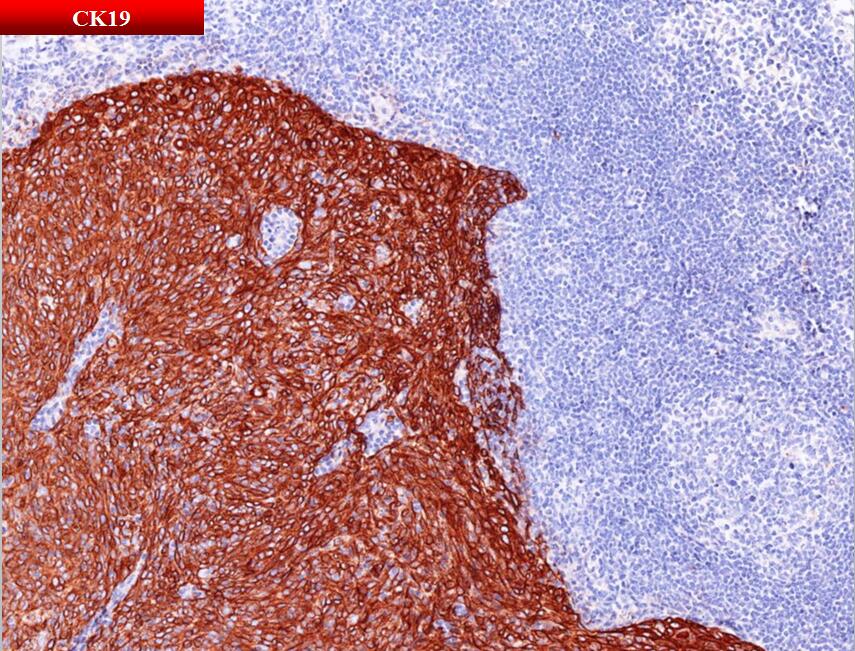

阳性: pan-Cytokeratin、CK5/6、CK19

阴性:CD20、CD5、CD117